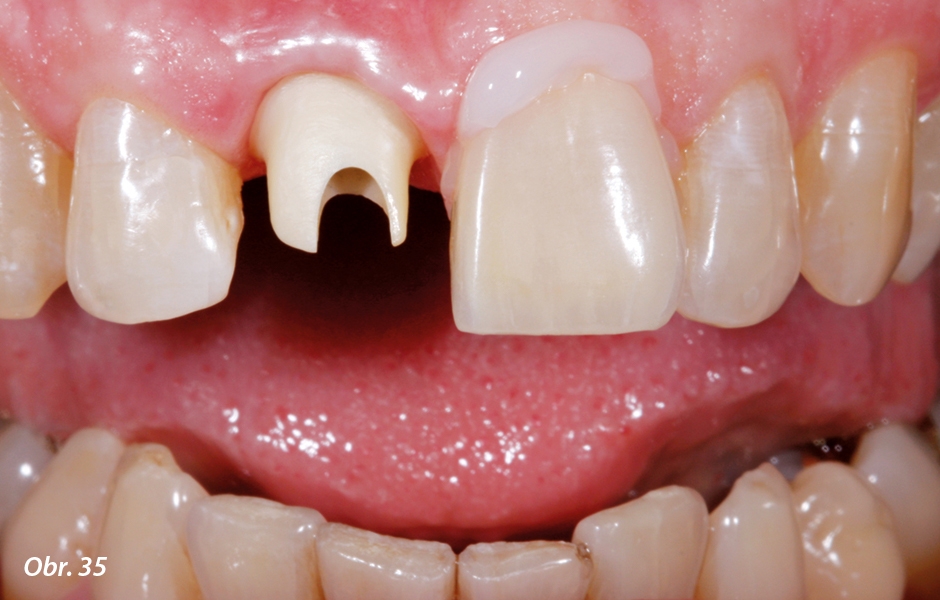

Následně byla vyzkoušena i keramická fazeta a zhodnocena z estetického a funkčního hlediska. Během toho byla nejprve na vlhkých zubech určena barva kompozitu použitého k fixaci fazety. Kvůli ověření vzhledu barvy a translucence fazety („estetická zkouška“) byl pomocí vodou rozpustných past Try-in, které barevně odpovídají vytvrzenému fixačnímu kompozitu, eliminován vzduch z fixační spáry („optické propojení“) (obr. 35). Tento vzduch ve fixační spáře by na základě jeho odlišných vlastností při lomu světla vedl k chybnému optickému působení.13–15 Prostřednictvím různých fixačních kompozitů, které se liší ve svém barevném tónu a intenzitě či případně opacitě, lze docílit maximálně pouze drobných úprav barvy fazety. Nepatrná tloušťka vrstvy fixačního kompozitu nedovoluje při výraznějším odklonu barvy fazety od stanoveného odstínu zpravidla žádné významné úpravy. Víceméně se tím dají korigovat pouze nepatrné rozdíly ve velmi omezeném rozsahu.16 Na druhou stranu ale z toho vyplývá i nebezpečí, že volbou špatného fixačního kompozitu (jako např. bílé opakní barvy) dojde esteticky ke zničení barvy a translucence perfektně vyrobené fazety. Estetická zkouška s Try-in pastou ve správném okamžiku je tak předpokladem pro zdařilý závěr ošetření. Aby se zamezilo přesušení zubů a s ním spojené reverzibilní zesvětlení a opakně působící vzhled,17–19 musí tato estetická kontrola samozřejmě probíhat na navlhčených zubech. Po očištění zubů a fazety od Try-in pasty proběhla následně ještě v rámci funkční zkoušky intraorální kontrola dosazení a okrajového uzávěru fazety.

Závěrečným vrstvením byla fazeta hotova

Vzhledem k tenké a translucentní vrstvě si lze jasně povšimnout, že výsledná barva nasazené keramické fazety je v tomto případě závislá především na barvě napreparovaného zubního pahýlu

Estetická zkouška keramické fazety na zubu 21 s použitím Try-in pasty